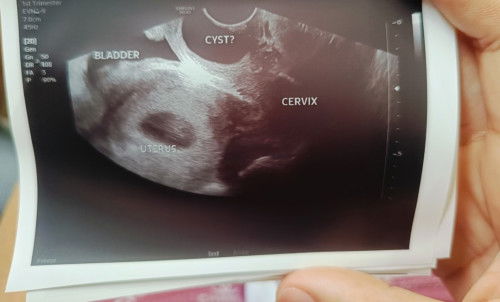

Vaginal cyst

Sino po ba mga may vaginal cyst dito? Paano po ba to nagagamot and ano po ang cause nito? May findings kasi sa ultrasound ko na may vaginal cyst daw ako. Patulong naman po. Baka makaapekto kay baby. Thank you po sa mga sasagot.